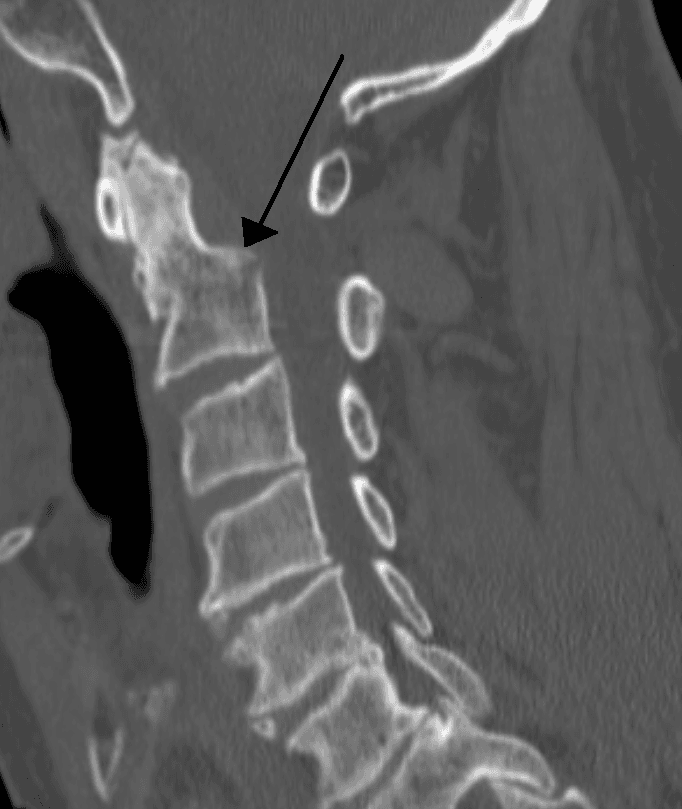

Un traumatisme cervical désigne tout traumatisme atteignant les structures du cou. Un tel traumatisme peut être isolé ou associé à d'autres dans le cas d'un polytraumatisé. Un traumatisme cervical est potentiellement grave car le cou est une partie du corps où de nombreuses structures jouant un rôle physiologique important sont présentes et relativement exposées : carotide, larynx, moelle épinière. Lorsque ces structures sont atteintes, le recours urgent à une prise en charge chirurgicale est impératif. Les lésions traumatiques de la colonne vertébrale cervicale sont des causes communes de décès et de handicap. Elles varient en gravité de : simples lésions des parties molles ; à la paralysie ou au décès ; avec ou sans fractures ou luxations graves. Les lésions traumatiques de la colonne vertébrale cervicale ne sont souvent reconnues qu'en salle d'urgence. Elles doivent faire l'objet d'un bilan soigneux et être prises en charge de manière à en minimiser les séquelles (pas de minerve routinière). Un diagnostic sans retard, une contention vraie plutôt qu'une « immobilisation », la préservation ou la restauration de la fonction de la moelle épinière et des racines, et la stabilisation définitive de la lésion sont les clés de la réussite de la prise en charge de telles lésions. Les fractures et « instabilité » du rachis cervical supérieur (zone du cou) présentent des caractéristiques un peu différentes des fractures et luxations du rachis cervical de C3 à C7. Au moins (Bohlman HH et Boada E., 1993) : un tiers de toutes les lésions de la colonne cervicale sont en rapport avec un accident à véhicule motorisé ; un tiers en rapport avec une chute d'un lieu plus ou moins élevé, et ; le reste est le résultat d'accidents lors de pratiques sportives, de chute d'objets ou de blessures par arme à feu. La majorité de ces lésions est observée chez le sujet jeune et actif, adolescents ou jeune adulte. Le deuxième grand groupe (en termes d'incidence) concerne l'adulte sexagénaire ou septuagénaire, avec la spondylose ou la sténose qui exposent à de graves lésions en dépit de la faiblesse des forces mises en jeu au niveau de la colonne elle-même.